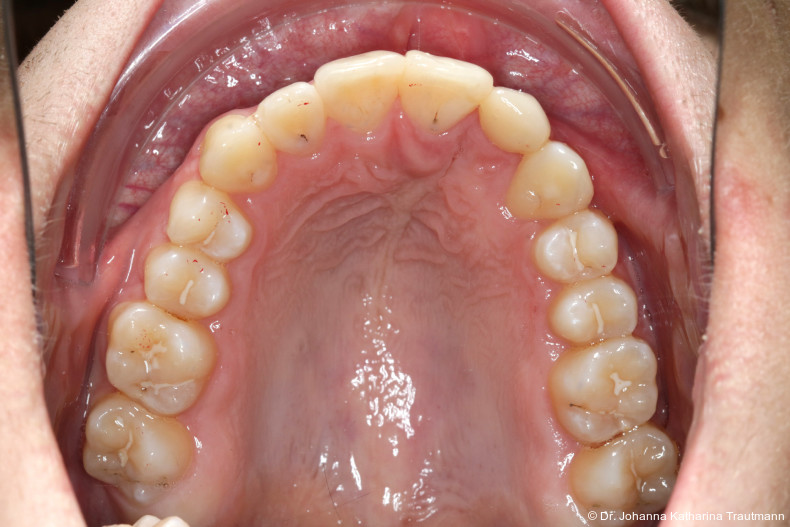

Das Fernröntgenseitenbild zeigte eine skelettale Klasse IIAnomalie mit einem Wits von 5,6 mm, bei einer tiefen Konfiguration (ML NL = 16,5°) mit bialveolär retrudierten Fronten (OK1NA = 5,9°; UK1NB = 10,4°), was sich auch in der Modellanalyse widerspiegelte. Hier zeigte sich zudem ein schmaler Oberkiefer mit multiplen Kippungen und Rotationen in der Front, einem hypoplastischem 22 sowie einer Mesialwanderung des 16. Des Weiteren zeigte sich eine asymmetrische Bisslage mit 1 PB distal rechts und ½ PB distal links bei einem Overjet von 2,5 mm sowie einem Overbite von 5 mm. Während im Unterkiefer bereits die zweite Zahnwechsel phase begonnen hatte, zeigte sich im Oberkiefer noch kein Wechsel in den Stützzonen. Gerade bei Patienten mit Spaltbildungen ist eine engmaschige Überwachung des Durchbruchs der oberen Eckzähne essenziell. Während bei der Allgemeinbevölkerung die Prävalenz von verlagerten Eckzähnen bei ca. 2,8 Prozent liegt2, ist diese bei Patienten mit Lippen-Kiefer-Gaumen-Spalten um den Faktor 10 erhöht.3, 4 Als klassische Risikofaktoren gelten zudem Platzmangel, transversale Enge aber auch Fehlstellungen, Nichtanlagen oder Hypoplasien der zweiten Schneidezähne. Diese übernehmen normalerweise die Funktion der Leitschiene für den S-förmigen Durchbruch der Eckzähne. Im vorliegenden Patientenfall kommen also mehrere Risikofaktoren für eine Verlagerung zusammen, was die rechtzeitige Diagnostik zur Abklärung einer Durchbruchsproblematik rechtfertigt. Da im Spaltbereich auch zusätzlich ein ausgeprägtes Knochendefizit vorliegen könnte, sollte auch immer die Option einer sekundären Osteoplastik abgewogen werden, deren Indikation und Timing optimal zum Durchbruch der Canini angepasst werden sollte.5

Zur genaueren Diagnostik der Lage beziehungen der Eckzähne und des Knochenangebotes im Spaltbereich kann neben den kieferorthopädi schen diagnostischen Unterlagen laut der S2 kLeitlinie Dentale digitale Volumentomografie6 auf eine dreidimensionale Bild gebung zurückgegriffen werden. In dieser zeigte sich eine vestibuläre Verlagerung des 13, eine palatinale Verlagerung des 23, sowie ein deutliches Knochendefizit im Spaltbereich mesial des hypoplastischen 22 (Abb. 2). Nach Auswertung der 3D-Daten erschien aufgrund der palatinalen Lage des 23 eine invasive Operation wie eine sekundäre Osteoplastik keinen entscheidenden Vorteil für die weitere Be handlung zu haben. In Rücksprache mit der Mund-Kiefer-Gesichtschirurgie der UMG wurde daher auf die OP verzichtet und initial die kieferorthopädische Therapie in den Vordergrund gestellt.